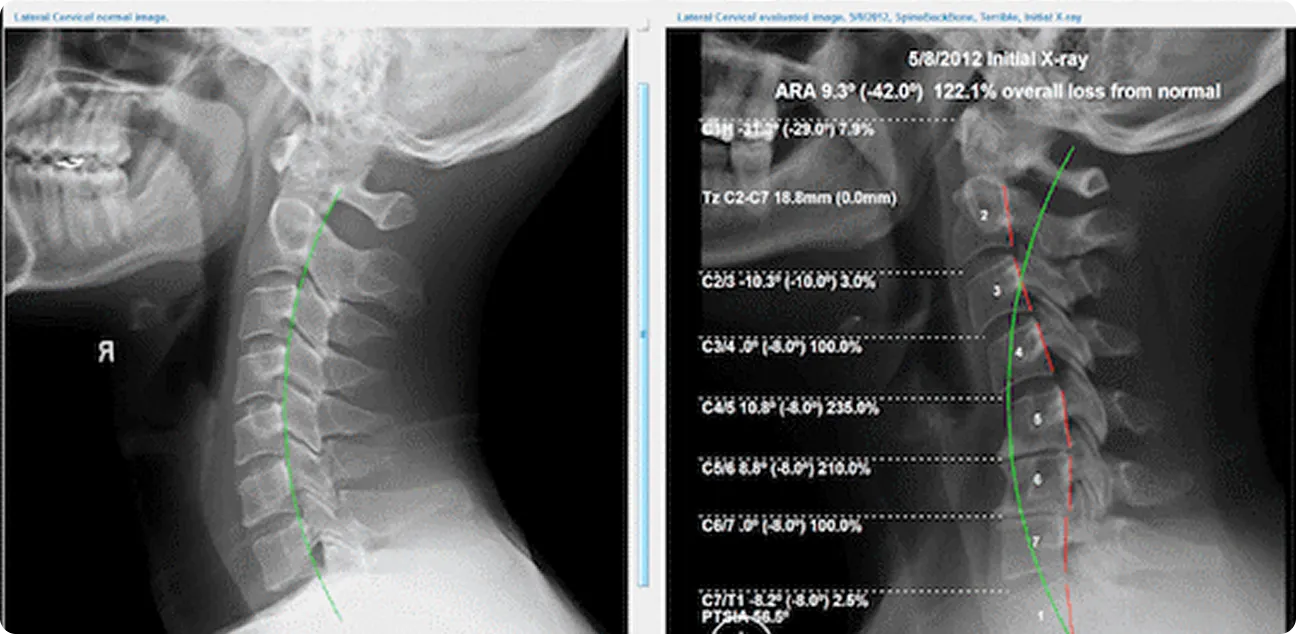

During your first chiropractic visit, your chiropractor will take a detailed medical history and perform a physical exam. They may also use diagnostic imaging, such as X-rays, to evaluate your condition further. Based on their findings, they will create a treatment plan that may include spinal adjustments, massage, and other therapies. Your chiropractor will explain the procedures and answer any questions you have before starting treatment.